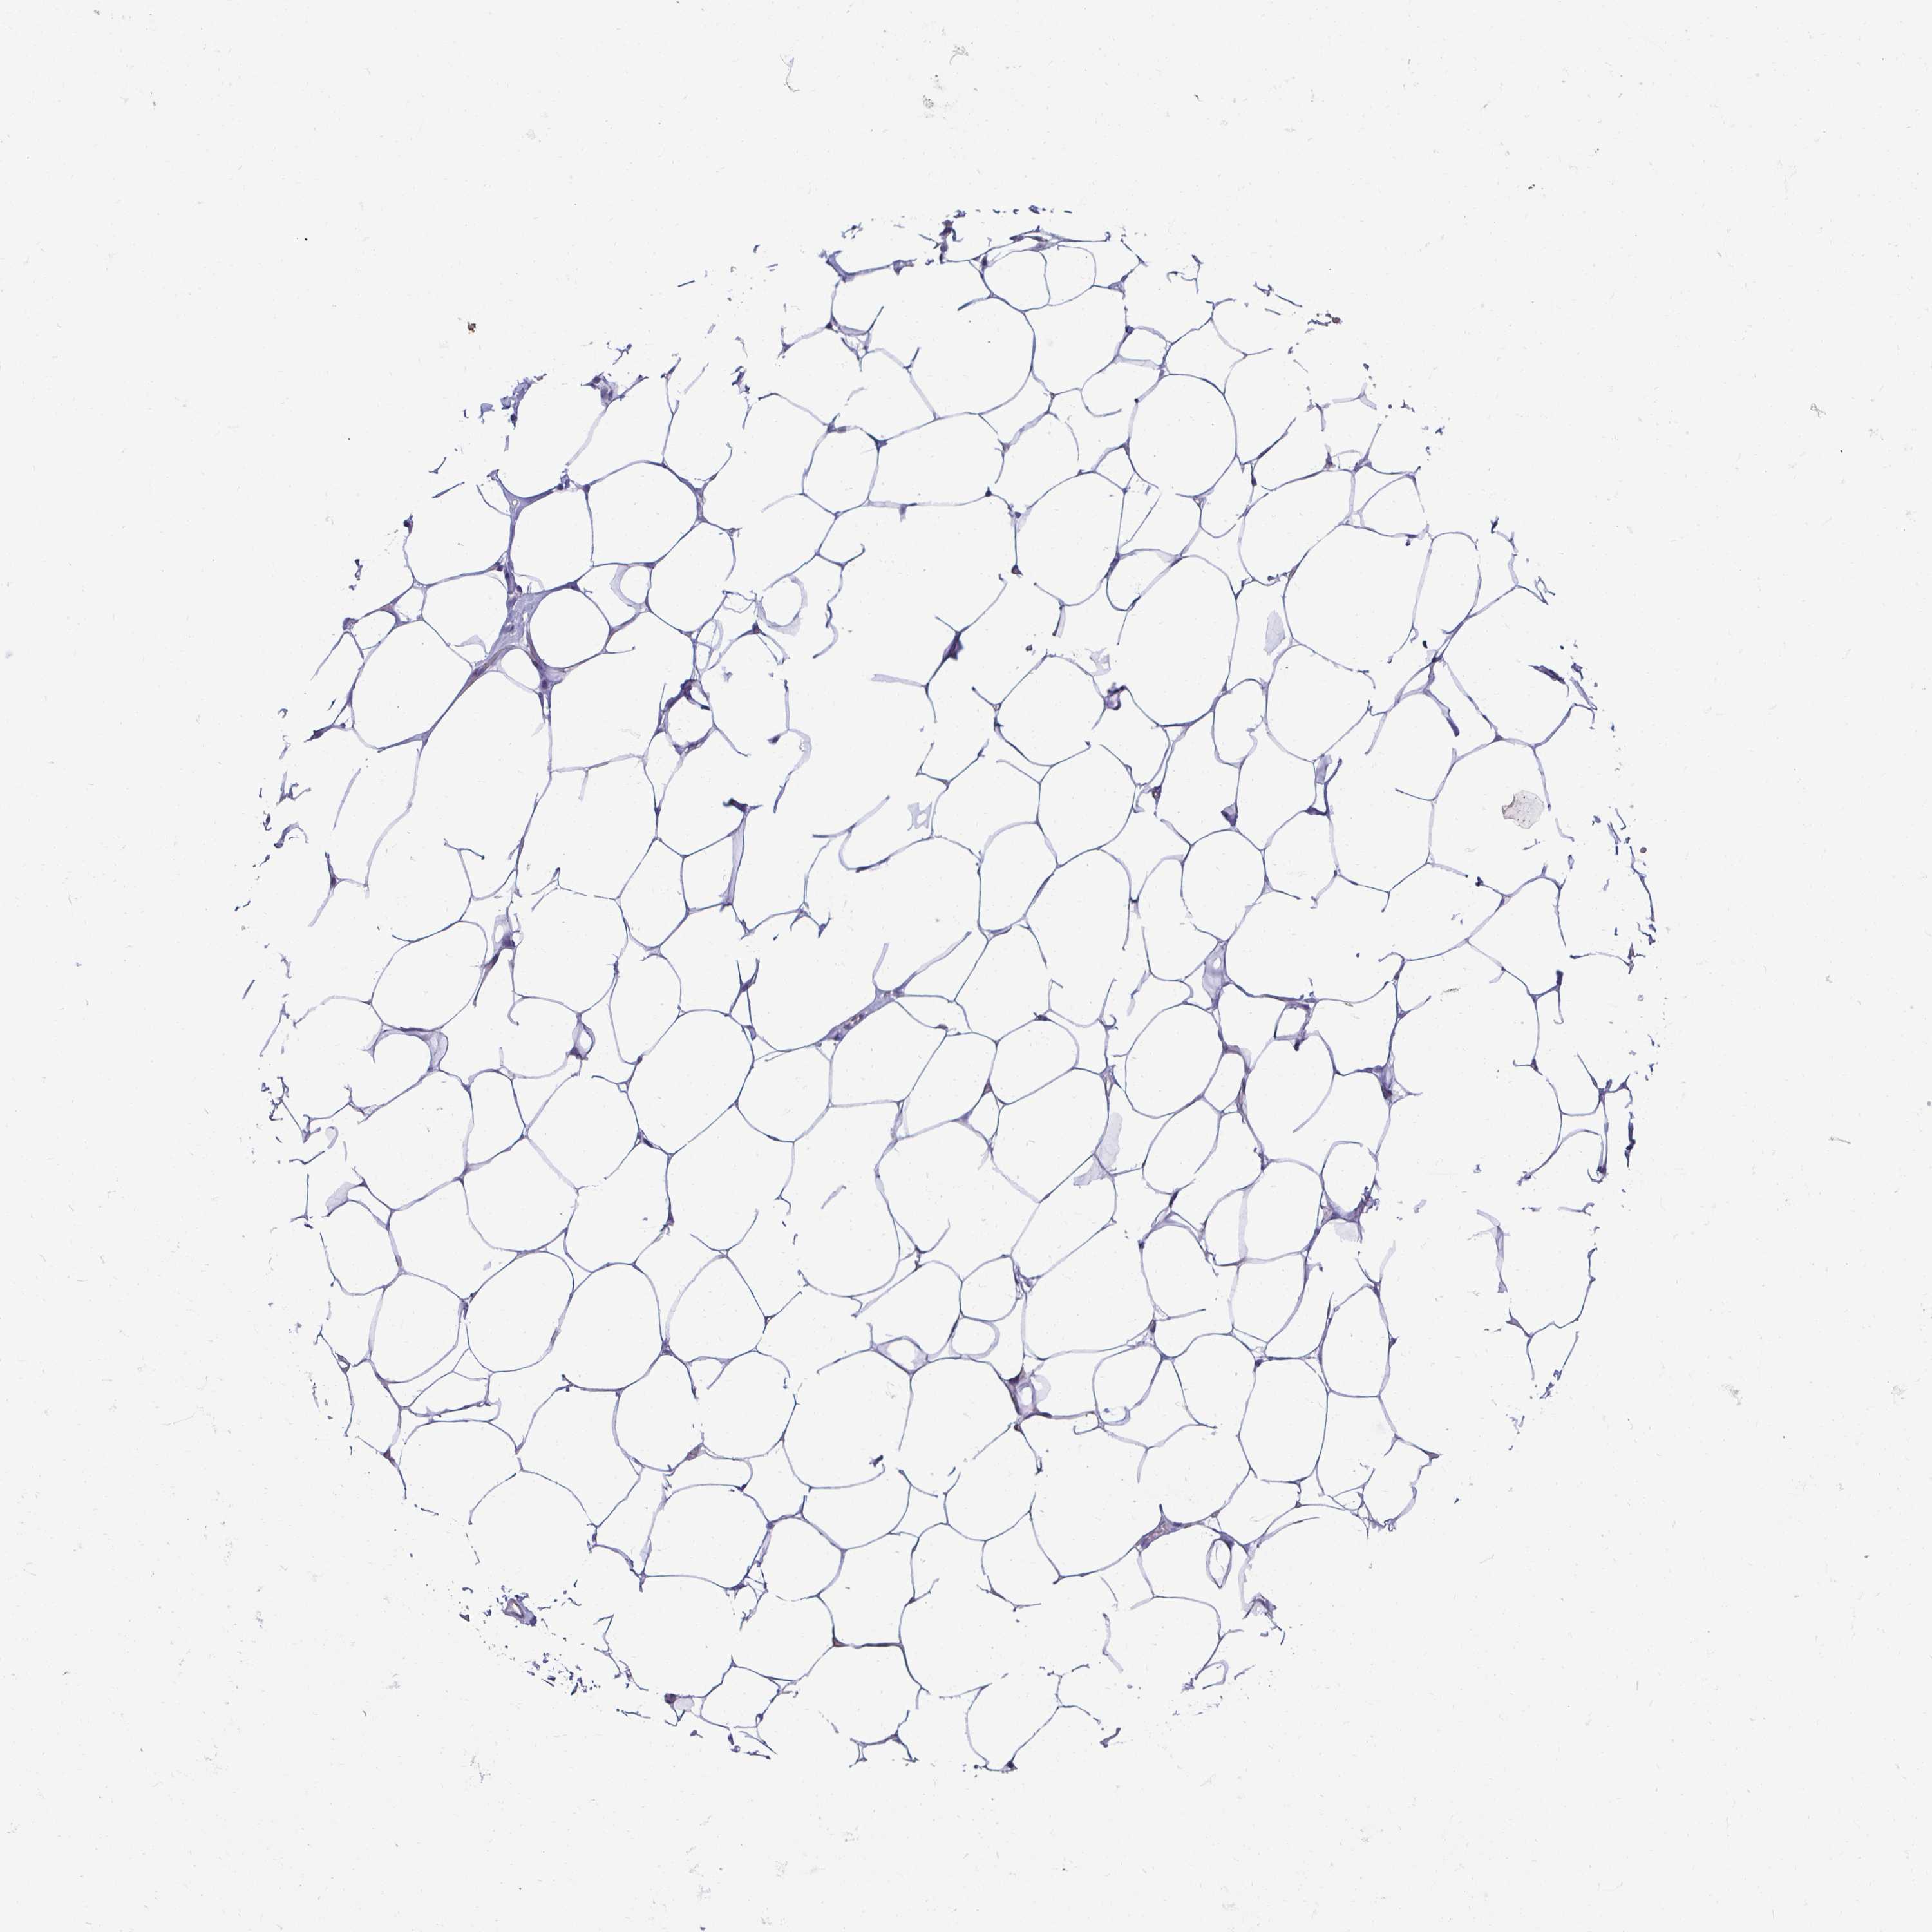

BREAST - Antibody stainingi

Antibody staining in the annotated cell types in the current human tissue is reported as not detected, low, medium, or high, based on conventional immunohistochemistry profiling in selected tissues. This score is based on the combination of the staining intensity and fraction of stained cells.

Each image is clickable and will lead to virtual microscopy that enables deeper exploration of all samples and also displays staining intensity scores, fraction scores and subcellular localization as well as patient and tissue information for each sample.

Antibody HPA027062Antibody CAB010059

Adipocytes Not detectedNot detected

Glandular cells Not detected-

Myoepithelial cells Not detected-